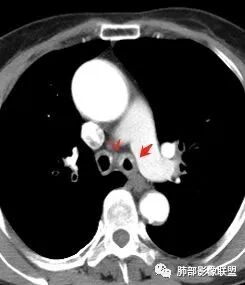

患者,女,64岁,反复咳嗽、咳痰、胸闷10年,加重2周。气管支气管及两肺下叶 支气管弥漫性的环状增厚,管腔扩张,管腔感觉比较松弛。第一感觉,气管支气管淀粉样变。鉴别诊断,1、支气管内膜结核,肺内散在一些支气管的播散病灶,粟粒结节为主,形态比较单一。2、复发性的多软骨炎,就得了解一下其他部位,有没有多个部位的软骨炎。这个病人右侧胸廓缩小,升主动脉明显的扩张,其横径明显的超过了降主动脉。

南边:肺部有肺气肿支气管腔狭窄淀粉样变性?复发性多软骨炎?血管炎?慢支?结核?曲霉菌?南边:一般还是淀粉样变性与复发性多软骨炎鉴别其次就是支气管骨化症,但是骨化下朝上,且壁结节状钙化明显,本例不太支持。至于结核、曲霉菌?1.结核,一般不会这么广泛,支气管壁狭窄后扩张2.曲霉菌可以这么广泛,但是支气管壁管腔扩张,而且附近脂肪间隙有炎性反应,不太支持;3.血管炎,一般合并肺内有病灶,但是声带受累,放待排;4.软骨炎一般全身受累,例如耳廓等;而且膜部不受累,不太支持;倾向于淀粉样变性;淀粉分很多型,气管支气管是最常见的。尘缘:影像上生理性钙化与支气管骨化无法区别,镜检也不好鉴别,需要依赖活检,看粘膜中是否合并炎性改变(淋巴细胞,组织细胞等炎性细胞侵润)来鉴别Coke with ice:经常看到的这种是老年性肺改变,又称年龄相关肺改变。气管和支气管弥漫性软骨钙化,常见老年女性。尘缘:支气管骨化症很罕见的,所以绝大多数还是生理性钙化。对于老年人,无临床症状的钙化,还是基本上都是生理性钙化,无临床意义。大雄:如果管壁钙化伴明显增厚 影像还是提示一下建议支气管镜稳妥些